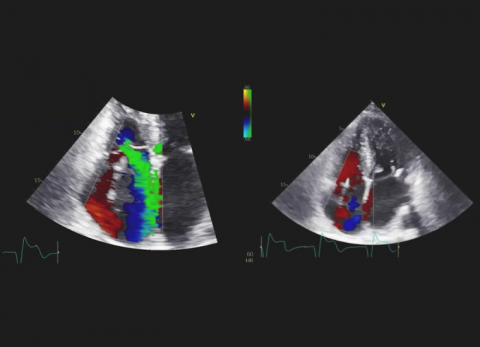

prof. dr hab. n. med. Zbigniew GąsiorPacjentka z kardiomiopatią przerostową, z napadowym migotaniem przedsionków, po implantacji ICD oraz przezskórnym zamknięciu uszka lewego przedsionka.